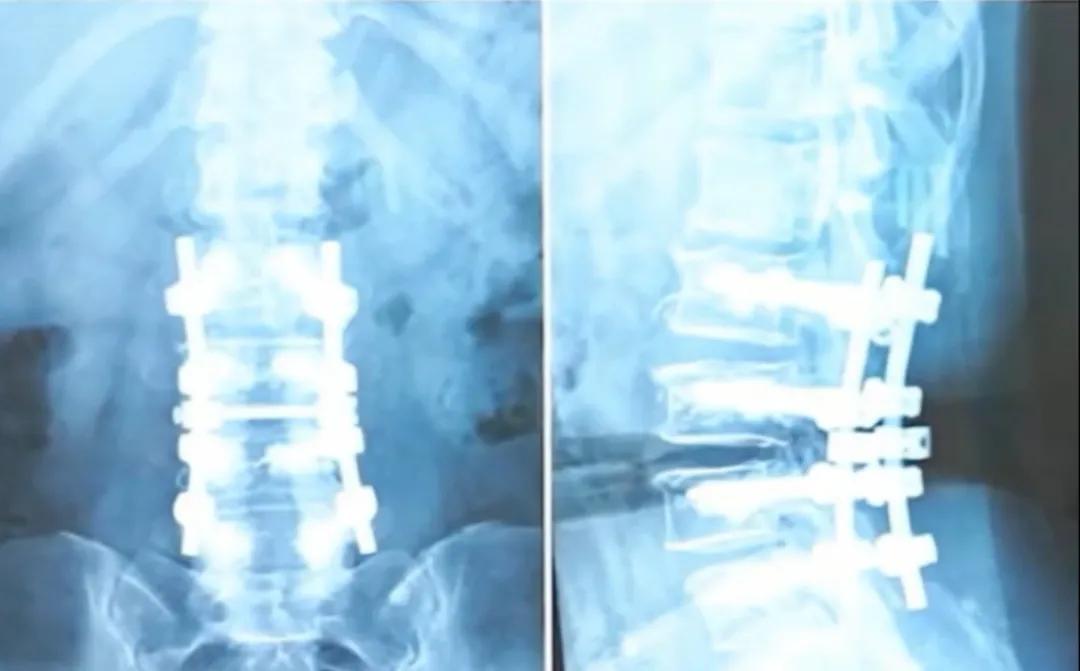

Как, например, пациентка старше 50 лет из видео, которая перенесла операцию по поводу тяжелого стеноза позвоночного канала и остеопороза. Для обеспечения стабильности позвоночника доктор Ван установил ей 4 пары (всего 8) винтов и выполнил вертебропластику костным цементом. Хотя такая операция может показаться масштабной, гибкость ее поясничного отдела после вмешательства осталась хорошей, и она даже может коснуться руками пола.